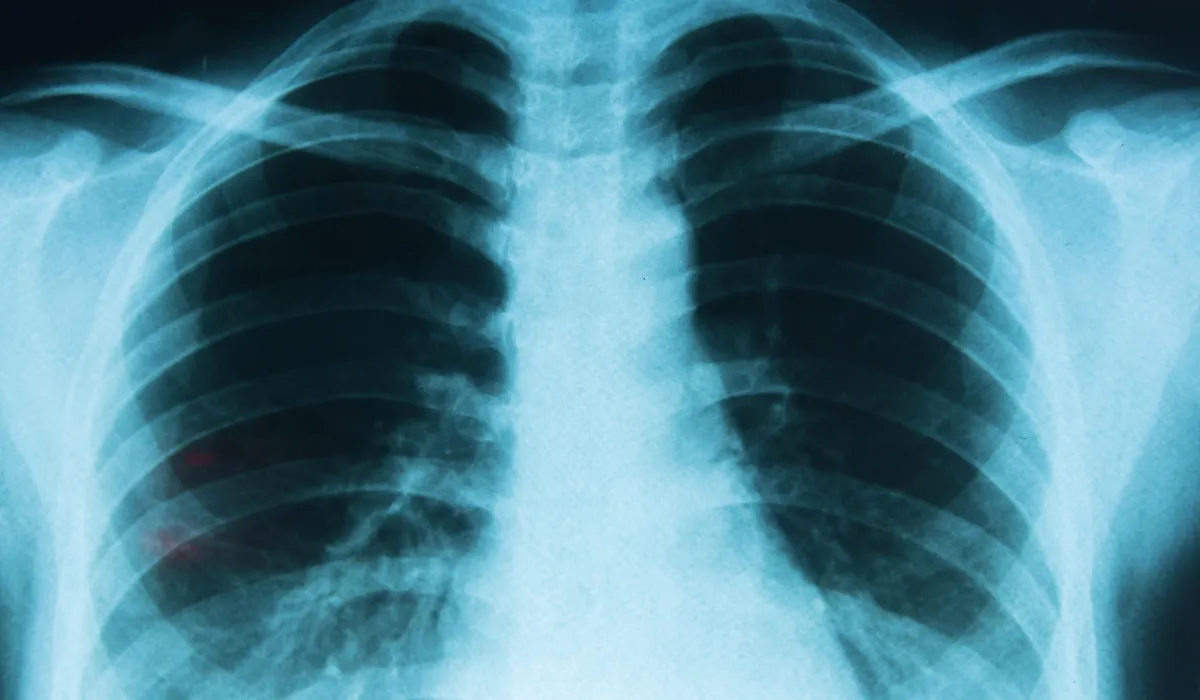

La contaminación del aire y su vínculo con los distintos tipos de cáncer de pulmón, según un nuevo estudio

Un reciente estudio internacional analizó cómo la contaminación del aire puede influir en el desarrollo de los distintos subtipos de cáncer de pulmón. La investigación fue liderada por el Instituto de Salud Global de Barcelona (ISGlobal), en colaboración con la American Cancer Society (ACS), y aporta nueva información sobre los riesgos asociados a la exposición prolongada a contaminantes atmosféricos.

El cáncer de pulmón se divide principalmente en dos grandes tipos: el microcítico, menos frecuente pero más agresivo y estrechamente ligado al tabaquismo, y el no microcítico, que es el más común.

Dentro del cáncer no microcítico se incluyen subtipos como el adenocarcinoma, el carcinoma escamoso y el carcinoma de células grandes, que se diferencian por el tipo de células afectadas y la zona del pulmón donde se desarrollan.